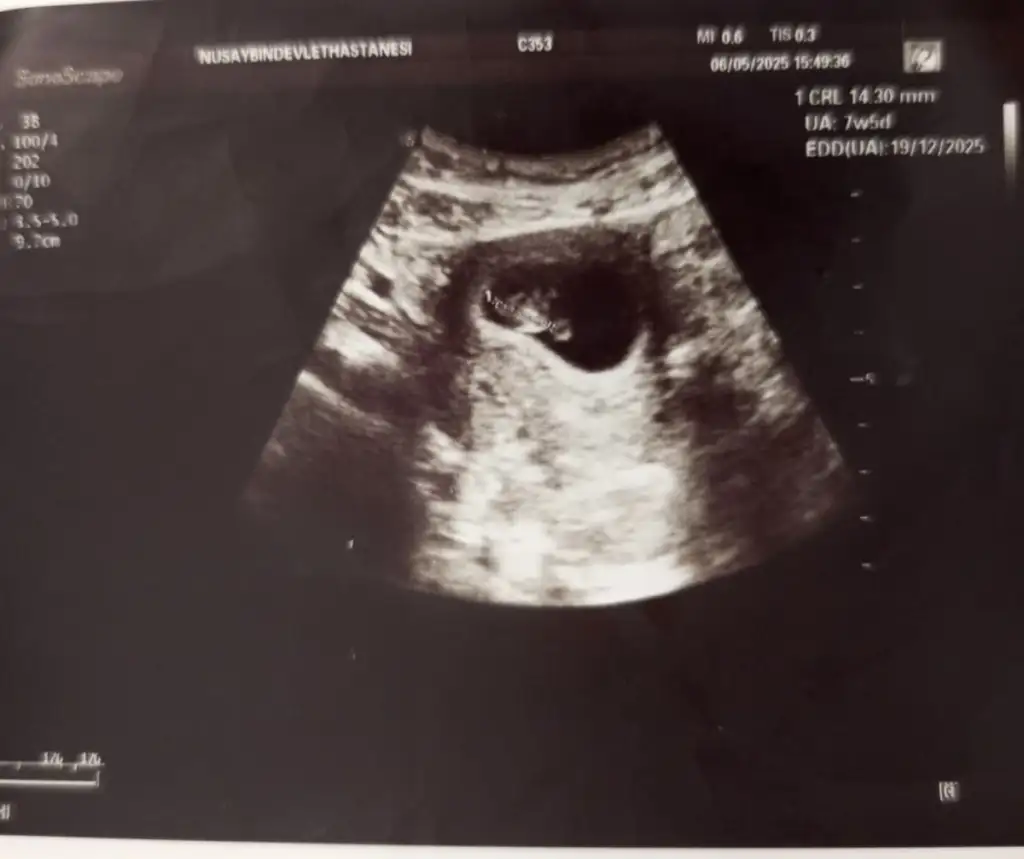

Merhaba, benim bebeğimde 10+4 bir tahmin yapılabiliyor mu acaba 🥰